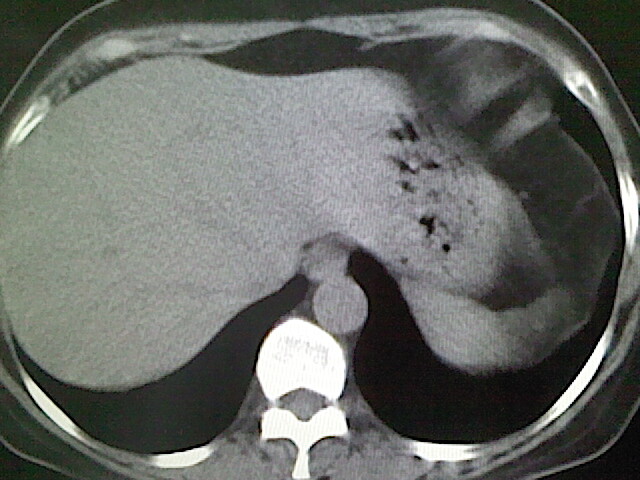

女,52岁,咳嗽,咳痰多日